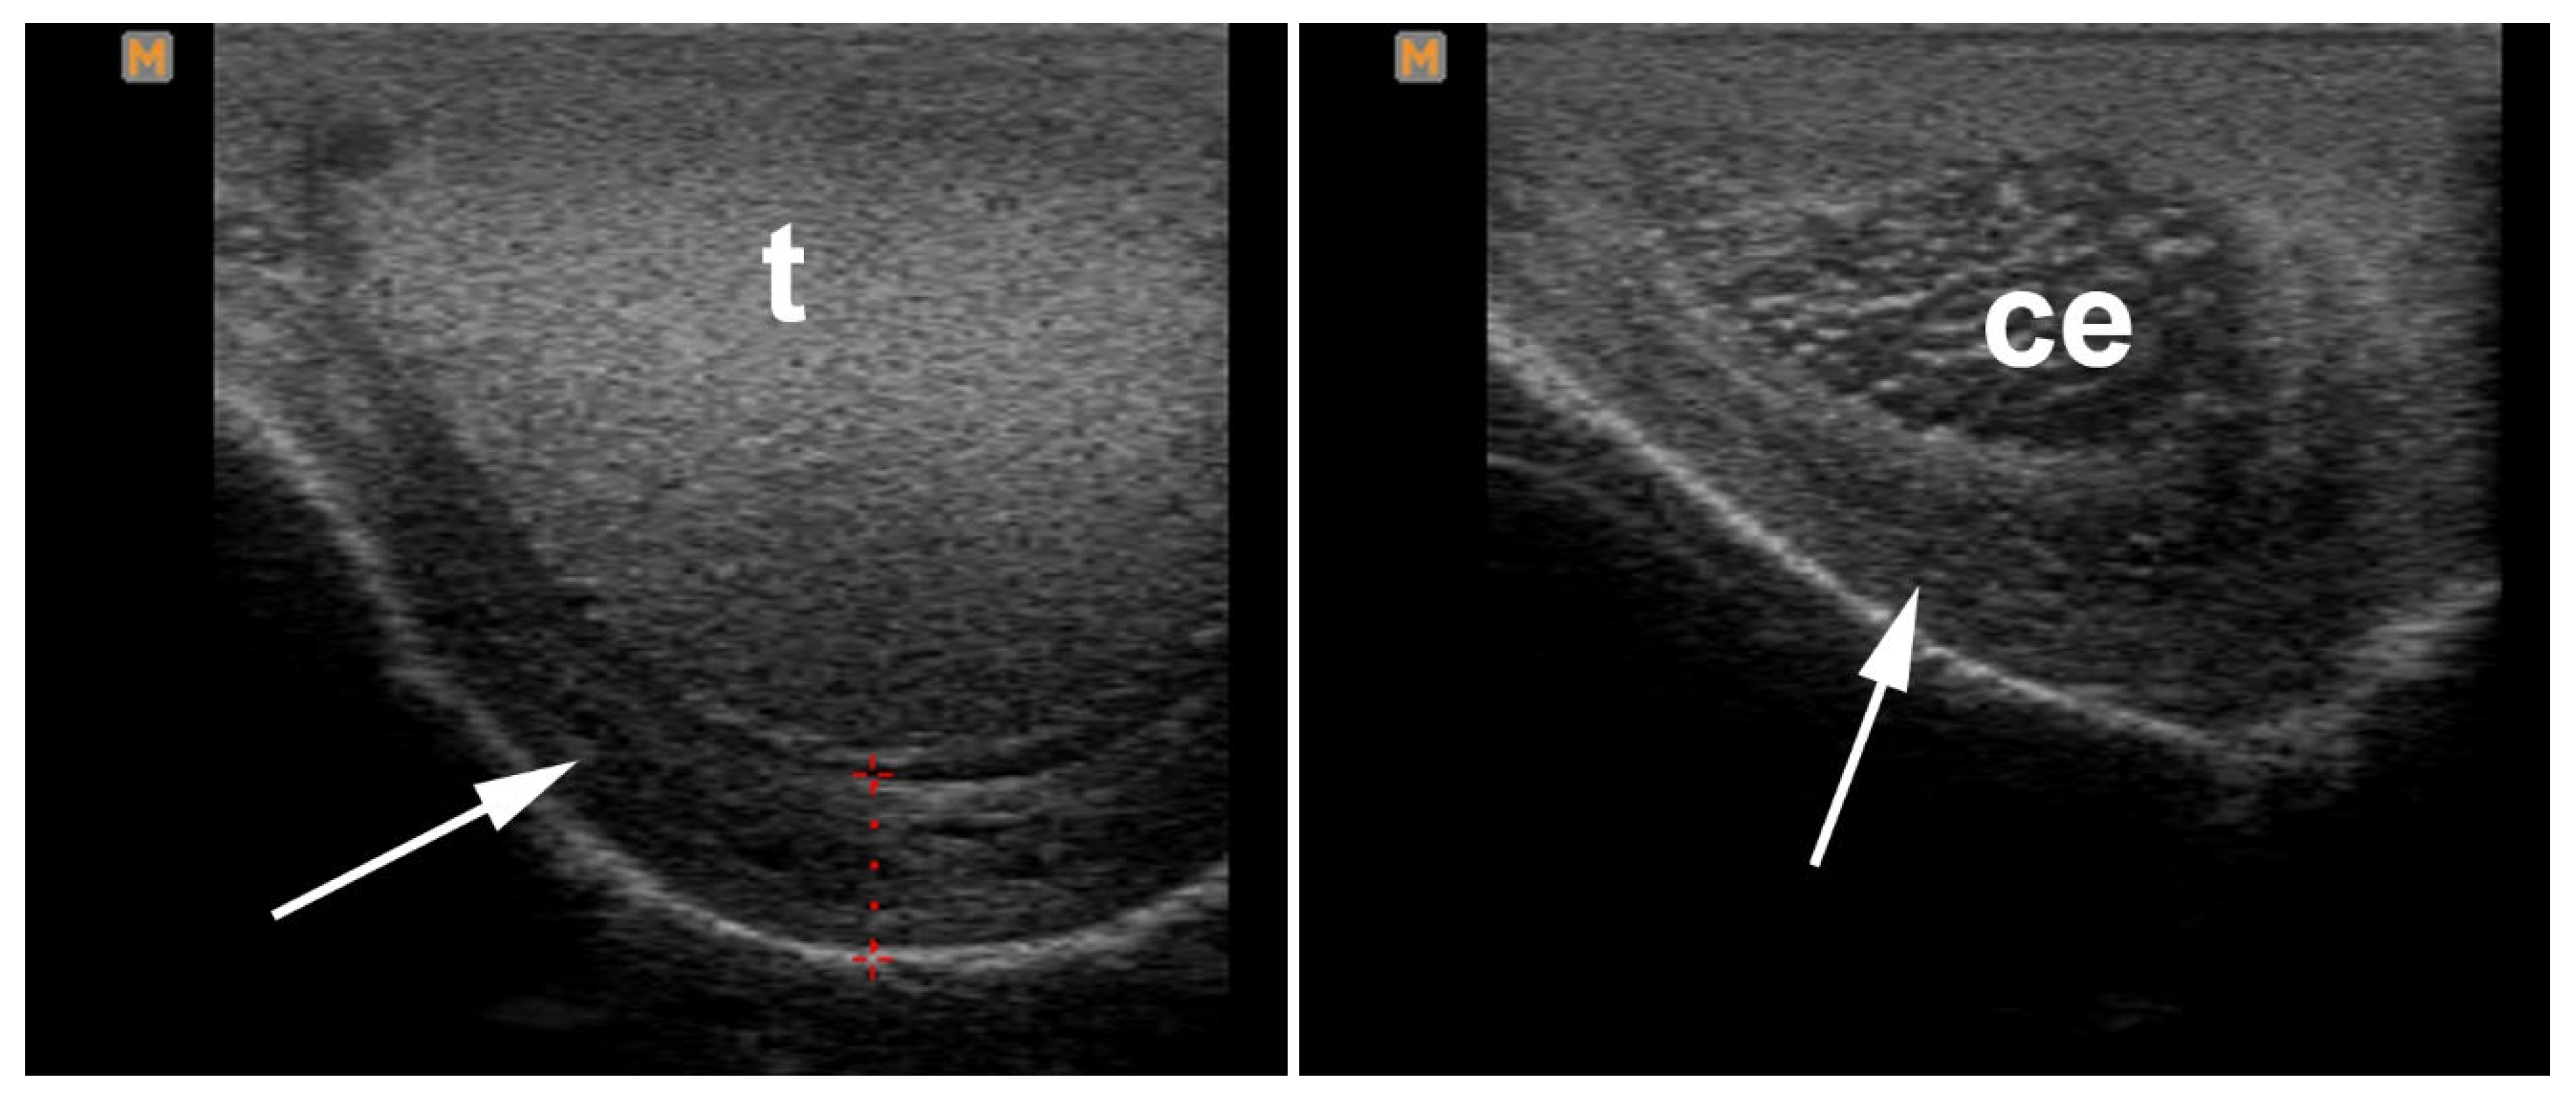

4.4. Orchitis and Epididymitis

5.1. Hydrocele

5.2. Pyocele